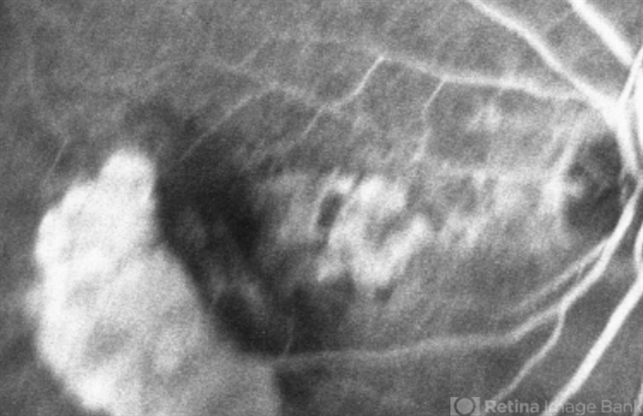

- retinal pigment epithelium (RPE) tear, wet age-related macular degeneration (wet AMD), choroidal neovascular membrane (CNVM)

- Scanning laser ophthalmoscope

- Mid Phase Fluorescein Angiogram: The scrolled and redundant RPE just temporal to the fovea blocks underlying choroidal fluorescence. The absent RPE, more temporally, results in a window defect with intense hyperfluorescence.